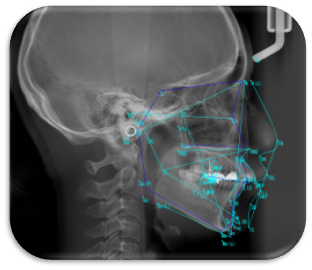

歯科クリニック中村は、より精度の高い検査や精密な診察行うために様々な先進的な医療機器(歯科用CTやレーザー機器やクリーニング用のEMS社Air-Flowまた全身管理の為のモニター、高性能拡大鏡等)を取り入れて、患者さんをお迎えしております。

日本成人矯正歯学会会員でもある、副院長がお子さんから大人までの歯並びにも対応しているため一つのクリニックで治療を完結することができます。